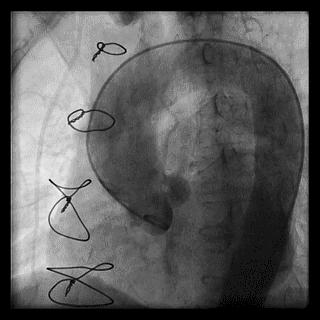

食管后起源右锁骨下动脉是一种较为少见的变异类型,发生率约为0.5%,食管后起源右锁骨下动脉是在右颈总动脉、左颈总动脉和左锁骨下动脉发出后直接起源于主动脉,随后绕行于食管的后方(图4)。由于食管后起源右锁骨下动脉进入主动脉的位置过于靠后,因此操作导引钢丝时非常容易进入降主动脉,此时前送造影导管至右锁骨动脉在主动脉的入口部,通过逆时针旋转导管使导管尖端指向升主动脉方向后再前送导丝。但即使应用上述方法也很难使导丝到位,大多数情况下不得不更换为对侧桡动脉或股动脉路径。

图4 食管后起源右锁骨下动脉

图5 食管后起源右锁骨下动脉造影导管到位处理:先尝试常用方法,包括选用亲水涂层导丝、前送导丝时患者深吸气以拉直血管、利用造影导管的头端弯曲调整导丝的尖端走向、利用导管和导丝的相对运动前送导丝等等,努力将导丝送入升主动脉